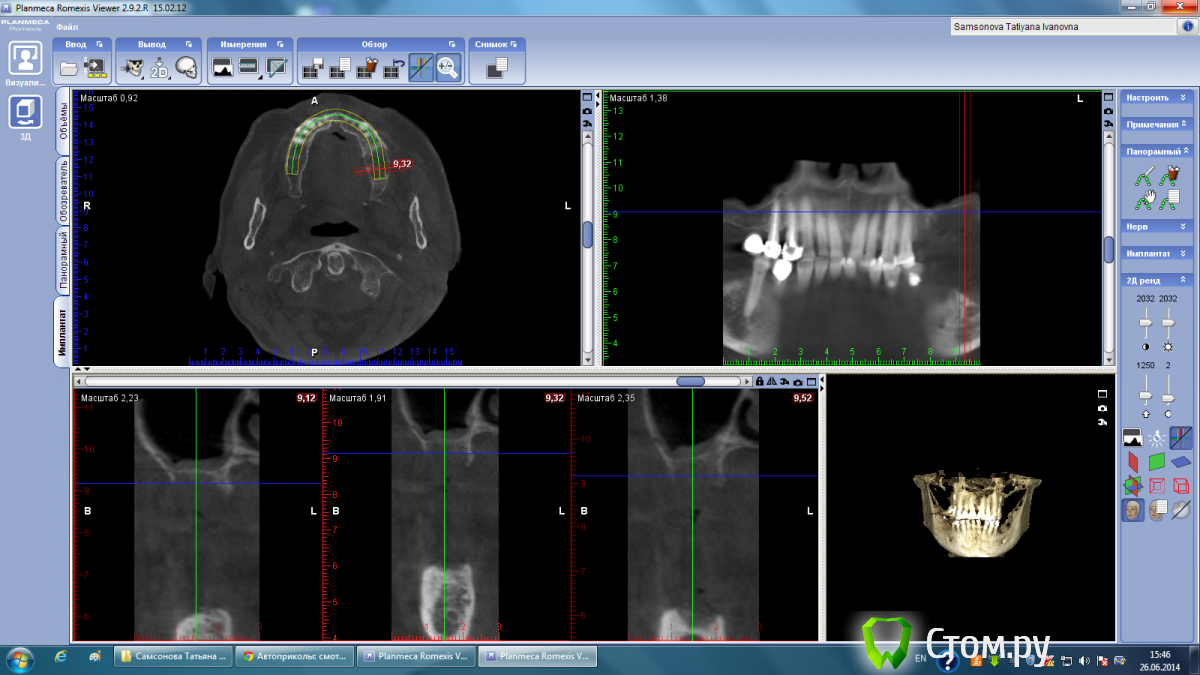

Тимур86 Опубликовано 26 июня, 2014 Поделиться Опубликовано 26 июня, 2014 пациентка пожилого возраста,хочется имплантов... Ссылка на комментарий

Mane Опубликовано 26 июня, 2014 Поделиться Опубликовано 26 июня, 2014 Вопрос автору - какие задачи вы ставите перед собой у этого пациента. Совершенно видно что нужен синус. Как вы считаете в пожилом возрасте не достаточно синуса и десны на втором этапе. И керамика розовая или чуть большеватые коронки. Оправдан здесь огород с костной пластикой. Если вертикалить то ламинаты или сетка или тайтэниум реинфорсд мембрэйн. Самое простое решение конечно же с сеткой. Но самые высокие риски прорезывания (у меня). Ждем ваши ответы. 1 Ссылка на комментарий

Тимур86 Опубликовано 26 июня, 2014 Автор Поделиться Опубликовано 26 июня, 2014 Ждем ваши ответы.согласен совершенно,естественно хочется минимизировать объемы костной пластики(и не только у пожилых пвциентов)но не снизит ли срок службы имплантов такое соотношение имплант/коронка в "псевдокости"? Ссылка на комментарий